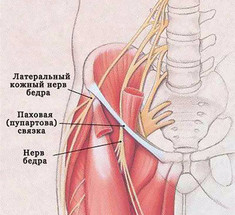

Упражнения при неврите наружного кожного нерва бедра

Экология здоровья: Надевая узкие брюки, вы можете спровоцировать синдром Бернарда-Рота или неврит наружного кожного...